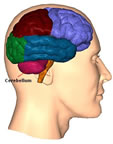

Serebellum-Beyincik

Serebellum

1-Omurgalı beyninin kas koordinasyonunu denetleyen kısmıdır.

2-Beyincik;Loplu bir yapıya sahiptir. Beyincik içindeki ak madde bir ağaç gibi boz madde içinde dağıldığı için bu kısma hayat ağacı denir.

Beyincik, vücuttaki kas faaliyetini düzenleyerek, vücudun dengeli hareketini sağlar. Beyinciği çıkartılan bir kuş dengesiz bir şekilde uçmaya çalışır.